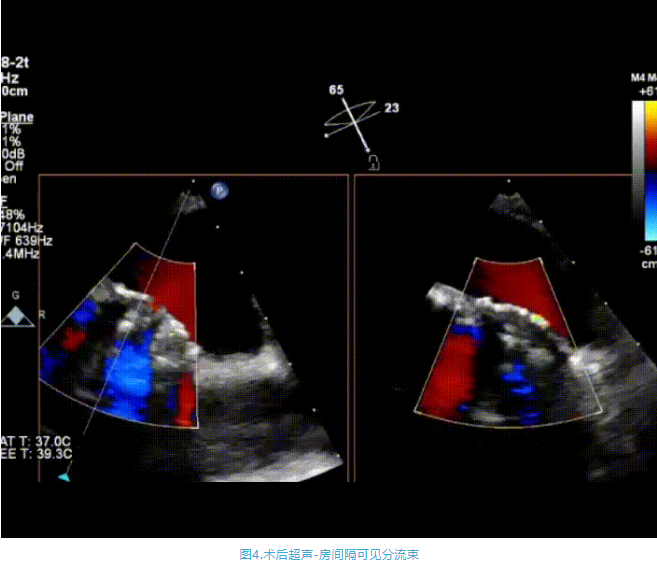

術(shù)中首先在局麻下穿刺股動(dòng)脈、股靜脈,完成心導(dǎo)管檢查評估后轉(zhuǎn)為全麻,在食道超聲引導(dǎo)下穿刺房間隔,穿刺成功后將加硬導(dǎo)絲送入左上肺靜脈建立軌道,根據(jù)患者病情行球囊預(yù)擴(kuò)張后植入6mm孔徑房間隔造孔支架,經(jīng)透視及食道超聲評估支架左右盤展開良好,夾持于房間隔兩側(cè),固定穩(wěn)定、位置良好,食道彩超顯示房水平右向左為主分流,分流孔直徑符合預(yù)期大小,心導(dǎo)管檢查評估達(dá)到預(yù)期效果,釋放造孔支架。術(shù)后12h患者下床活動(dòng),恢復(fù)順利,擬于近日完善術(shù)后評估后出院。

心房分流術(shù)是通過器械制造穩(wěn)定可控的心房間分流,適應(yīng)證包括藥物治療效果不佳的左心衰或肺動(dòng)脈高壓右心衰。本例患者為肺動(dòng)脈高壓右心衰,術(shù)中成功放置MicroFlux®造孔支架在房間隔理想位置上,創(chuàng)造穩(wěn)定可控的心房間分流(此例患者以右向左分流為主),在不顯著增加左心負(fù)擔(dān)的情況下,有效降低患者右心房壓力、緩解體循環(huán)淤血,增加左心輸出量,改善患者癥狀、活動(dòng)耐力和生存質(zhì)量。同時(shí),國內(nèi)外也已經(jīng)開展多項(xiàng)房間隔造孔支架在射血分?jǐn)?shù)保留、射血分?jǐn)?shù)中間值和射血分?jǐn)?shù)降低的左心衰患者中的臨床研究,結(jié)果顯示對于經(jīng)過充分的規(guī)范化藥物治療后仍控制不佳的患者,心房分流術(shù)可改善患者的癥狀及生存質(zhì)量?! ?/p>